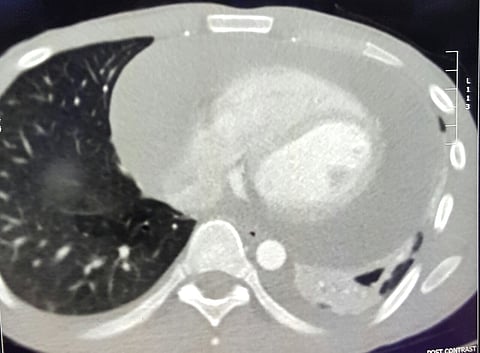

وأضاف: تم تشخيصه بالتخصصي بشكلٍ عاجل بعد إجراء اللازم بوجود تجمع حاد للسوائل والدم داخل الغشاء التيموري للقلب، مع التهاب الغشاء التيموري، وتقرر بموجبه إجراء جراحة عاجلة لتفريغ السوائل حول القلب لإنقاذ حياته.

وتابع: "تم التعامل فوراً مع الحالة، حيث لم يكن بالإمكان تخدير المريض بشكلٍ كامل؛ نتيجةً لحالته الحرجة جداً، وتقرر عمل فتحة واحدة صغيرة (3 سم) مباشرةً على القلب تحت التخدير الموضعي، حيث تم من خلالها فتح نافذة بالغشاء التيموري للقلب؛ لتفريغ ما يقارب اللتر ونصف اللتر سوائل من حول عضلة القلب، واستئصال جزء متورم من الغشاء التيموري".